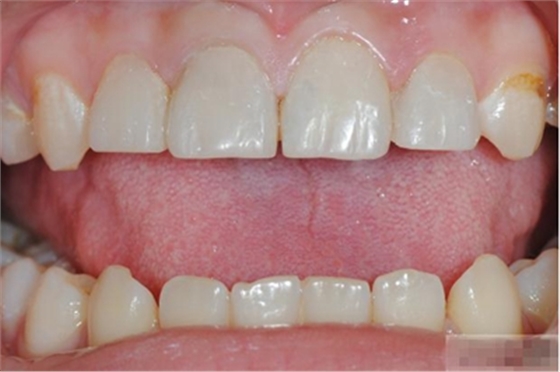

【主訴】上前牙充填物脫落兩個(gè)月

【病史】上前牙一年前行根管治療,充填物部分脫落,自覺影響美觀,從不敢笑,要求先行樹脂修復(fù)。(年齡:14歲)

【檢查】12,11,21,22,均行玻璃離子充填,各牙不同程度部分充填物脫落,探(—),叩(—),冷刺激無反應(yīng),無松動(dòng),牙齦顏色粉紅,質(zhì)地堅(jiān)實(shí)而有彈性,點(diǎn)彩正常,牙結(jié)石(—);牙髓活力測試無反應(yīng)。

【診斷】12,11,21,22牙體缺損

【充填完成】

1、樹脂貼面平齊牙齦邊緣是最佳設(shè)計(jì),或者使用齦上邊緣 。

2、釉質(zhì)邊緣要用橡皮輪拋光。拋光可以去除懸釉。這樣經(jīng)過車針打磨過的釉質(zhì)表面會(huì)更加均一,形成良好的邊緣封閉。

3、纖維樁通常深入到根管的1/2至2/3處。因?yàn)樽罴训恼辰有Чl(fā)生于根管的冠1/3和中1/3。由于根1/3的牙本質(zhì)小管往往不能充分敞開,此區(qū)域幾乎沒有粘接作用發(fā)生,所以,根管纖維樁放置的深度無需超過根中1/3。